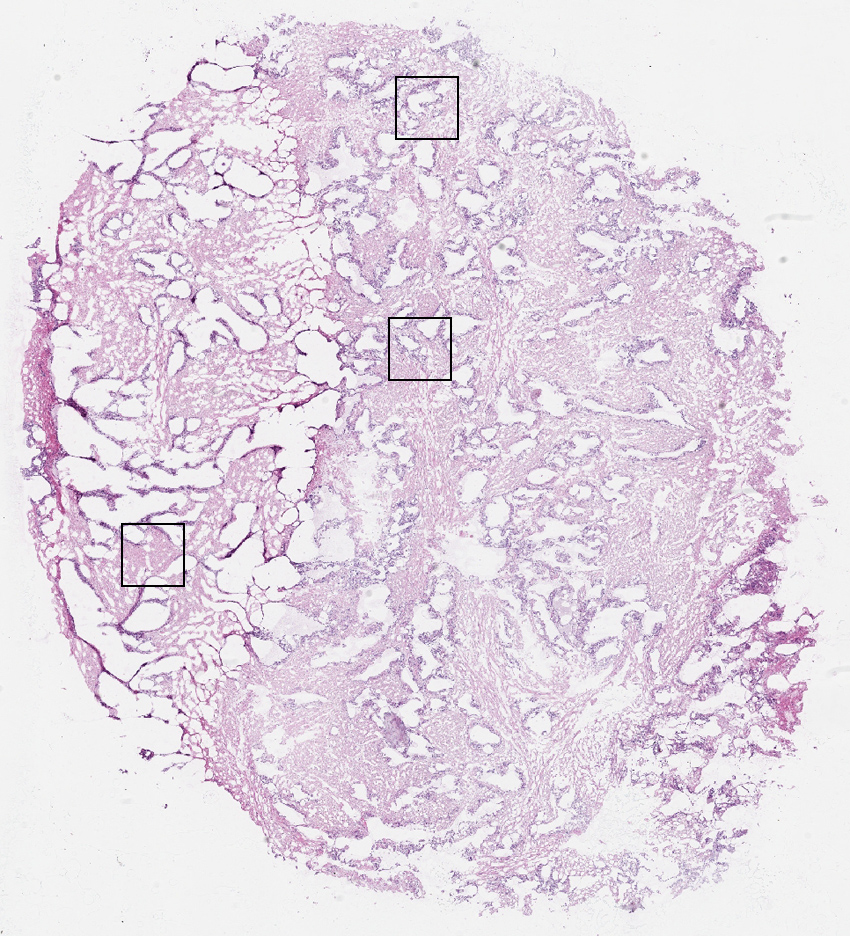

Glandular cells:

50

Smooth muscle cells:

45

Other cell types:

5